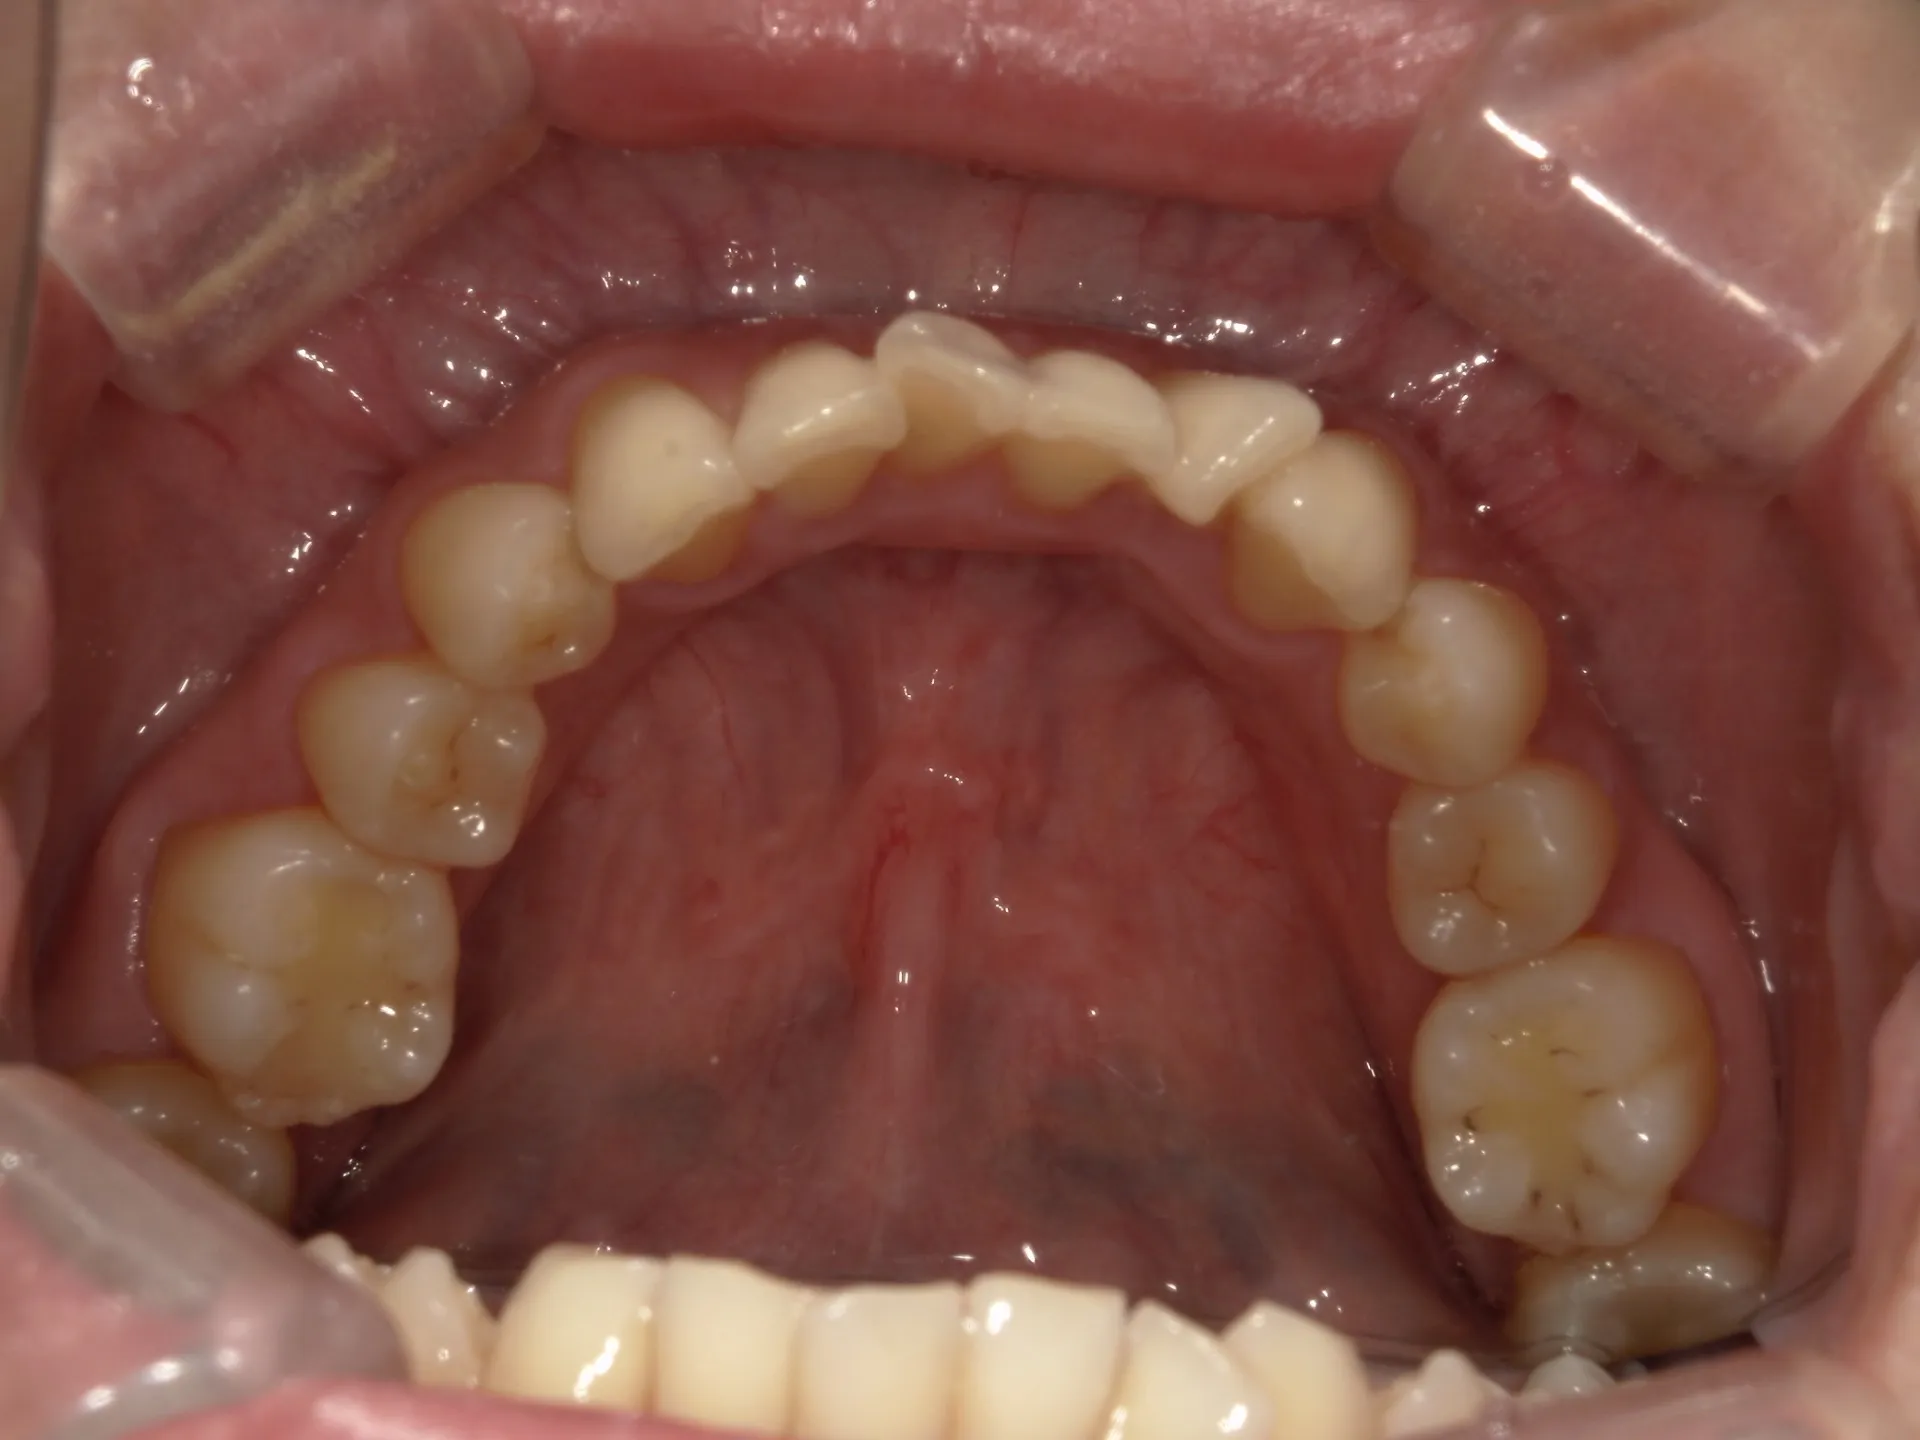

正面観

初診時

上の前歯が1本大きくねじれ、更にその歯に変色も見られました。

下の歯もスペースがなくガタついている状態の歯並びでした。